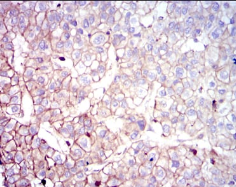

COTL1 Mouse Monoclonal antibody[5C8A5]

IHC    1/200 - 1/1000